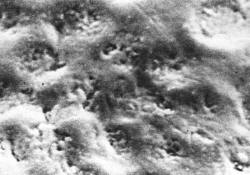

La figuras (izquierda)

muestran una sección longitudinal por desgaste, examinada

al microscopio con luz transmitida:

-

Zona superficial

(ZS): Es poco afectada porque recibe

minerales del cuerpo de la lesión

(1-2%

de porosidad)

-

Cuerpo de

la lesión (C):

Es el

área de mayor

desmineralización

(25-50%

de porosidad)

-

Zona

oscura

(ZD):

Desmineralización

(5-10%

de porosidad)

-

Zona

translúcida

(ZT):

No siempre está presente,

se encuentra en el avance

frontal

de la lesión,

ligeramente

más poroso

que el esmalte

sano,

la pérdida

de minerales

es del 1%

|

Ver fotografía derecha superior: Superficie de esmalte

vista con microscopio electrónico de barrido. |

| Esmalte

visto al microscopio electrónico de barrido |